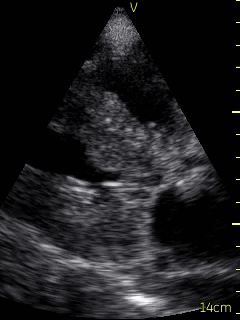

A bedside echocardiogram (VScan, GE) showed evidence of severe left ventricular and right ventricular thickening. Both atria were severely dilated. The mitral, tricuspid, and aortic valves appeared thickened. Myocardial speckling was not appreciated. Both the left and right ventricular function appeared to be moderately impaired.